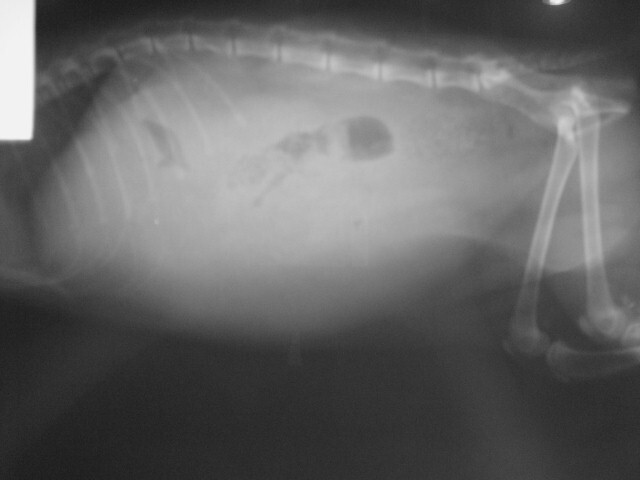

主題: 五甲南京路口 腹膜炎有腹水的貓咪 申請者姓名: 劉雅雲 花色: 申請日期: 2012-11-10 01:27:48 申請者部落格: 申請者臉書網址: 所在縣市/合作醫院: 高雄市/樂生動物醫院 治療費用: 6850元 需求人數: 8人 已結案 (2013-06-27 14:03:00) 報名人員: kelly(已付款)、MeiDan Wang(已付款)、Sky(已付款)、Sky(已付款)、Sky(已付款)、Sky(已付款)、Sky(已付款)、Sky(已付款)、 候補人員: 動物病情說明: 這是在五甲南京路誘捕結紮的貓咪, 麻醉後醫生發現貓咪有腹水的現象, 所以進行血檢與腹膜炎的檢驗. 在治療照顧下, 貓咪已抽過一次腹水, 但還是不敵腹膜炎的病魔, 當天使去了.

Fip貓的費用如下:

驗血 1500

貓FIV/FELV KIT 500

台灣基因貓FIP血液檢查_1550

穿刺放液術(腹腔)_600

住院__300 * 9 =2700 <10/23 - 10/31>

TOTAL=6850